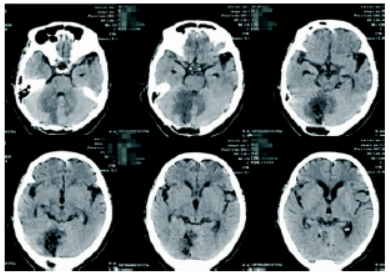

图2 患者的MRS提示:NAA明显下降,Cho明显升高

手术及病理:采取后正中入路,术中切开小脑皮层后可见灰白色肿瘤组织,质软,无包膜,边界不清,镜下肿瘤全切。术后及出院前复查头颅CT如图3、4。我院病理科病理结果提示T淋巴细胞增生性病变,倾向T细胞淋巴瘤,建议分子病理检测进一步确诊;免疫组化:圆形细胞CK-、GFAP-、CgA-、Syn-、S-100-、TTF-1-、LCA+、CD3弥漫+、CD56-、CD3阳性细胞Ki-67约60%,CD20和CD79α灶性+,CD68部分吞噬细

1588559019850236.png

图3 肿瘤切除术后复查